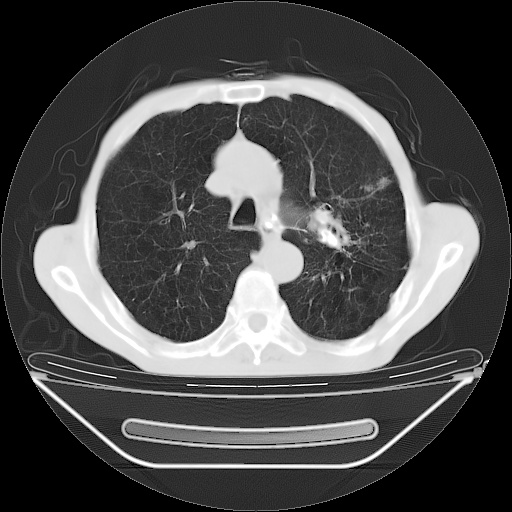

以下是引用zsl6918在2008-8-25 21:55:00的发言:[br]符合右肺周围性肺癌并肺内转移,左肺结核球。双肺肺气肿。腰椎附件转移。

以下是引用随光逐影在2008-8-25 22:03:00的发言:[br]1)考虑右肺下叶周围性肺癌并肺内转移,腰椎附件转移。2)左上肺结核(结核球形成)。3)双肺肺气肿(多发肺大泡形成)。4)双肺门区及纵隔内多发淋巴结钙化。